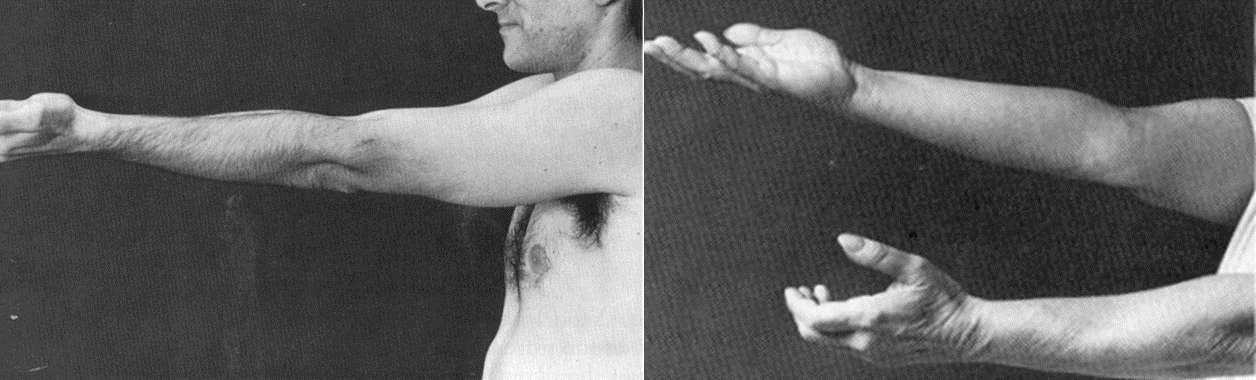

A- Spasticity: increased tone throughout range of motion, and then there is a sudden release (catch). Seen in UMN lesion. Spasticity is velocity dependent(sudden release).

B- Rigidity: increased tone throughout the range of motion. If intermittent and regular interruption to the movement gives jerky feeling, is called cogwheel rigidity, which is seen in extrapyramidal diseases such as Parkinson’s disease. Rigidity is not velocity dependent (continuous)

Hoffman’s sign is an involuntary flexion movement of the thumb and or index finger when the examiner flicks the fingernail of the middle finger down. This has sensitivity of 59% and a specificity of 49% to screen for upper motor neuron lesion (UMN lesions).